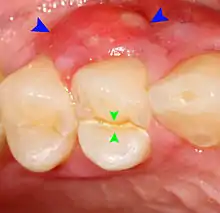

Food impaction

Food impaction occurs when food debris, especially fibrous food such as meat, becomes trapped between two teeth and is pushed into the gums during chewing.[6]: 125–135 The usual cause of food impaction is disruption of the normal interproximal contour or drifting of teeth so that a gap is created (an open contact). Decay can lead to collapse of part of the tooth, or a dental restoration may not accurately reproduce the contact point. Irritation, localized discomfort or mild pain and a feeling of pressure from between the two teeth results. The gingival papilla is swollen, tender and bleeds when touched. The pain occurs during and after eating, and may slowly disappear before being evoked again at the next meal,[nb 1] or relieved immediately by using a tooth pick or dental floss in the involved area.[6]: 125–135 A gingival or periodontal abscess may develop from this situation.[21]: 444–445

Periodontal abscesses are less common than apical abscesses, but are still frequent. The key difference between the two is that the pulp of the tooth tends to be alive, and will respond normally to pulp tests. However, an untreated periodontal abscess may still cause the pulp to die if it reaches the tooth apex in a periodontic-endodontic lesion. A periodontal abscess can occur as the result of tooth fracture, food packing into a periodontal pocket (with poorly shaped fillings), calculus build-up, and lowered immune responses (such as in diabetes). Periodontal abscess can also occur after periodontal scaling, which causes the gums to tighten around the teeth and trap debris in the pocket.[21]: 444–445 Toothache caused by a periodontal abscess is generally deep and throbbing. The oral mucosa covering an early periodontal abscess appears erythematous (red), swollen, shiny, and painful to touch.[22]